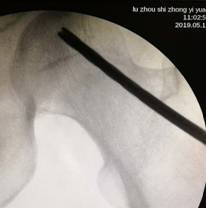

术中,为患者打通“隧道”,注入血小板